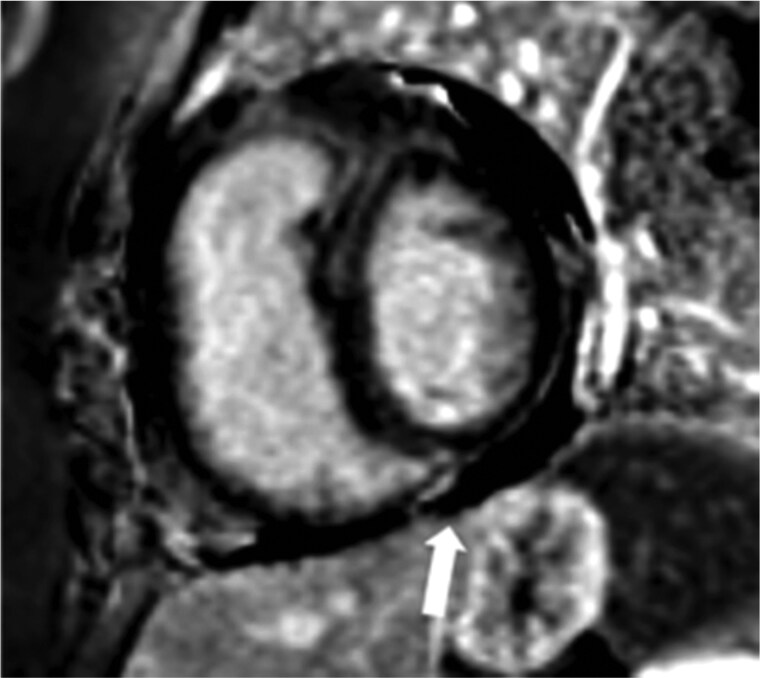

急性肺栓塞可以表现为一系列生理状态,从偶然发现到危及生命的右心衰。我们讨论了成像在准确和快速诊断中所起的关键作用。此外,影像学特征是评估表现严重程度的核心,允许适当的风险分层和护理升级。各种成像方式用于慢性血栓栓塞性肺动脉高压的管理的相对优势也进行了讨论。

Acute pulmonary emboli can manifest as a spectrum of physiological status ranging from an incidental finding to life threatening right heart failure. We discuss the crucial role imaging plays in the accurate and rapid diagnosis. In addition, imaging features are central in assessing the severity of the presentation allowing for appropriate risk stratification and escalation of care. The relative strengths of the various imaging modalities used in the management of chronic thromboembolic pulmonary hypertension are also discussed.